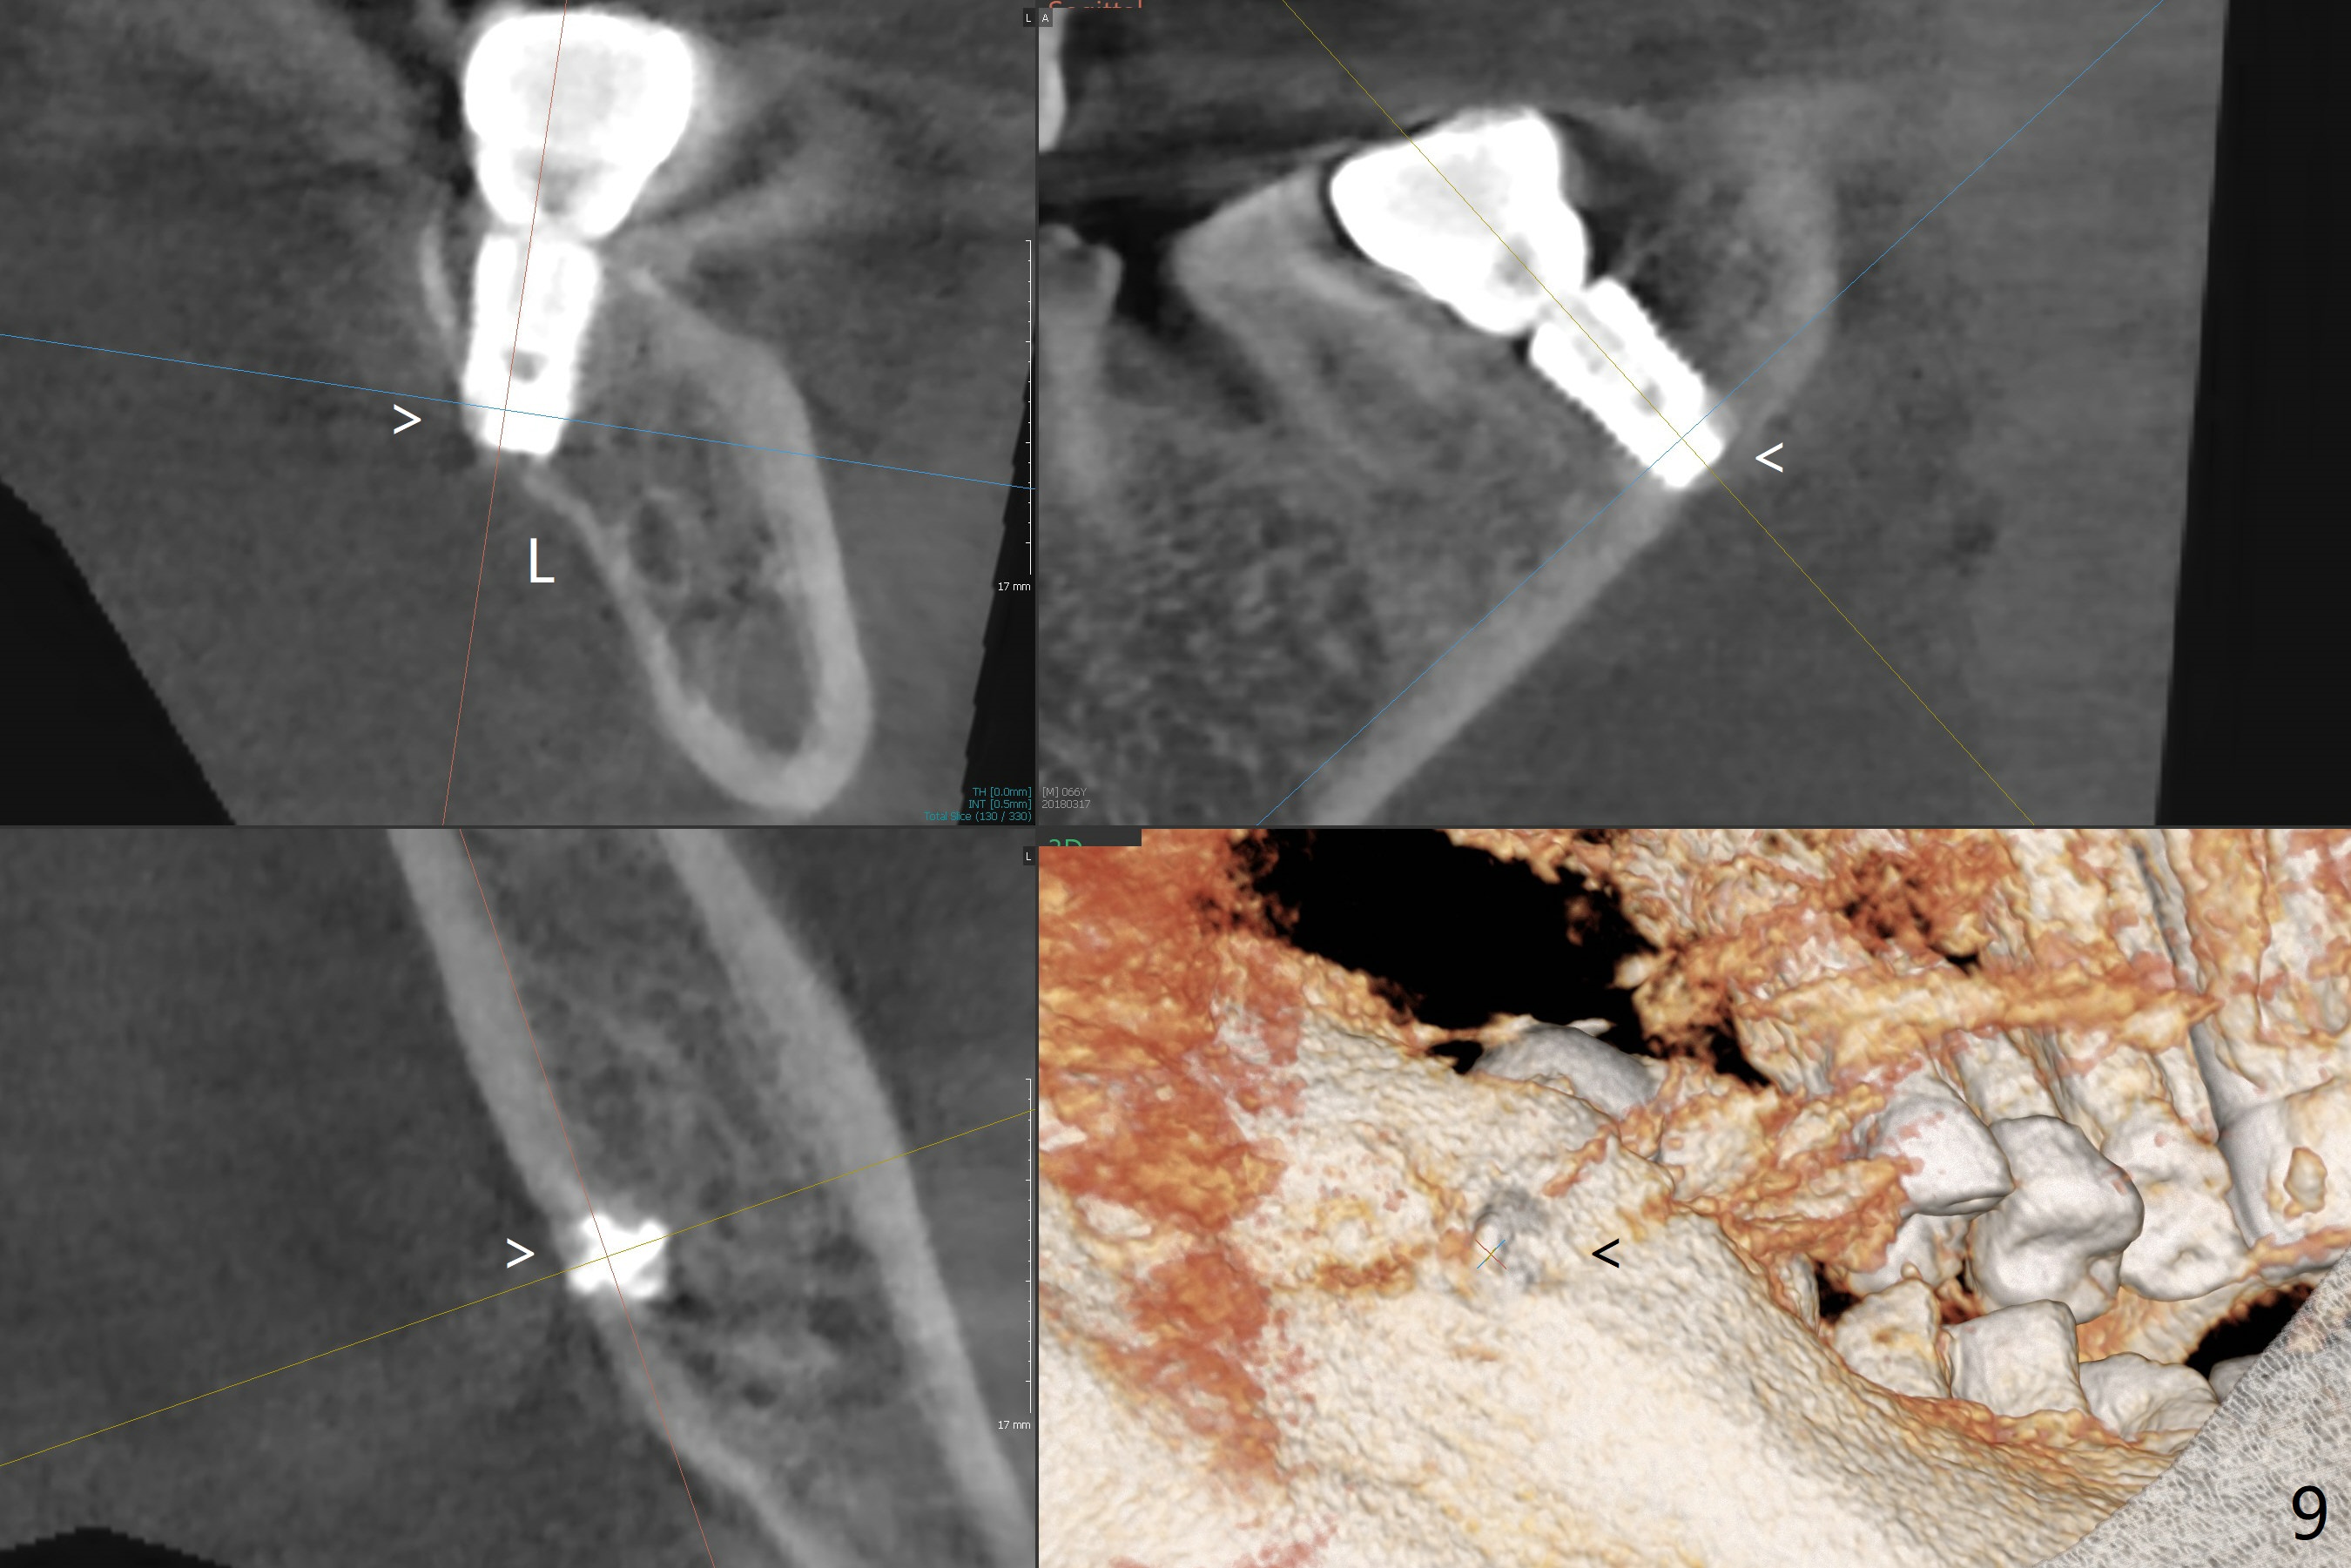

After extraction, curettage and Clindamycine gauzes in the sockets of the tooth #18 for 3 times, a 2 mm pilot drill makes initial osteotomy in the socket from 8 to 14 mm (Fig.1 (gingival level)). It appears that the osteotomy should move distal (Fig.1: red line, Fig.2 (17 mm)). After 5.9x10 mm drill, a 5.9 mm tap is placed (Fig.3). There is 4 mm clearance. Following 6.4x10 mm drill for 2 mm deeper, a 6.4x10 mm implant is placed with 60 Ncm. The implant plateau is level with the lingual crest, while the mesiobuccodistal bone is low. Autogenous bone mixed with Osteogen is placed in the defect area, followed by insertion of a 6.8x4(4) mm abutment (Fig.5). Collagen dressing is placed on the top of the graft. An immediate provisional is fabricated to close the remaining socket. Impression is taken 7 months postop (Fig.6). There seems to be no bone loss 23 months post cementation without opposing teeth (Fig.7) in spite of severe periodontitis at #19 (Fig.8 (25 months post cementation)). More surprising is the asymptomatic lingual (L) plate perforation, revealed by CT (Fig.9 arrowheads).